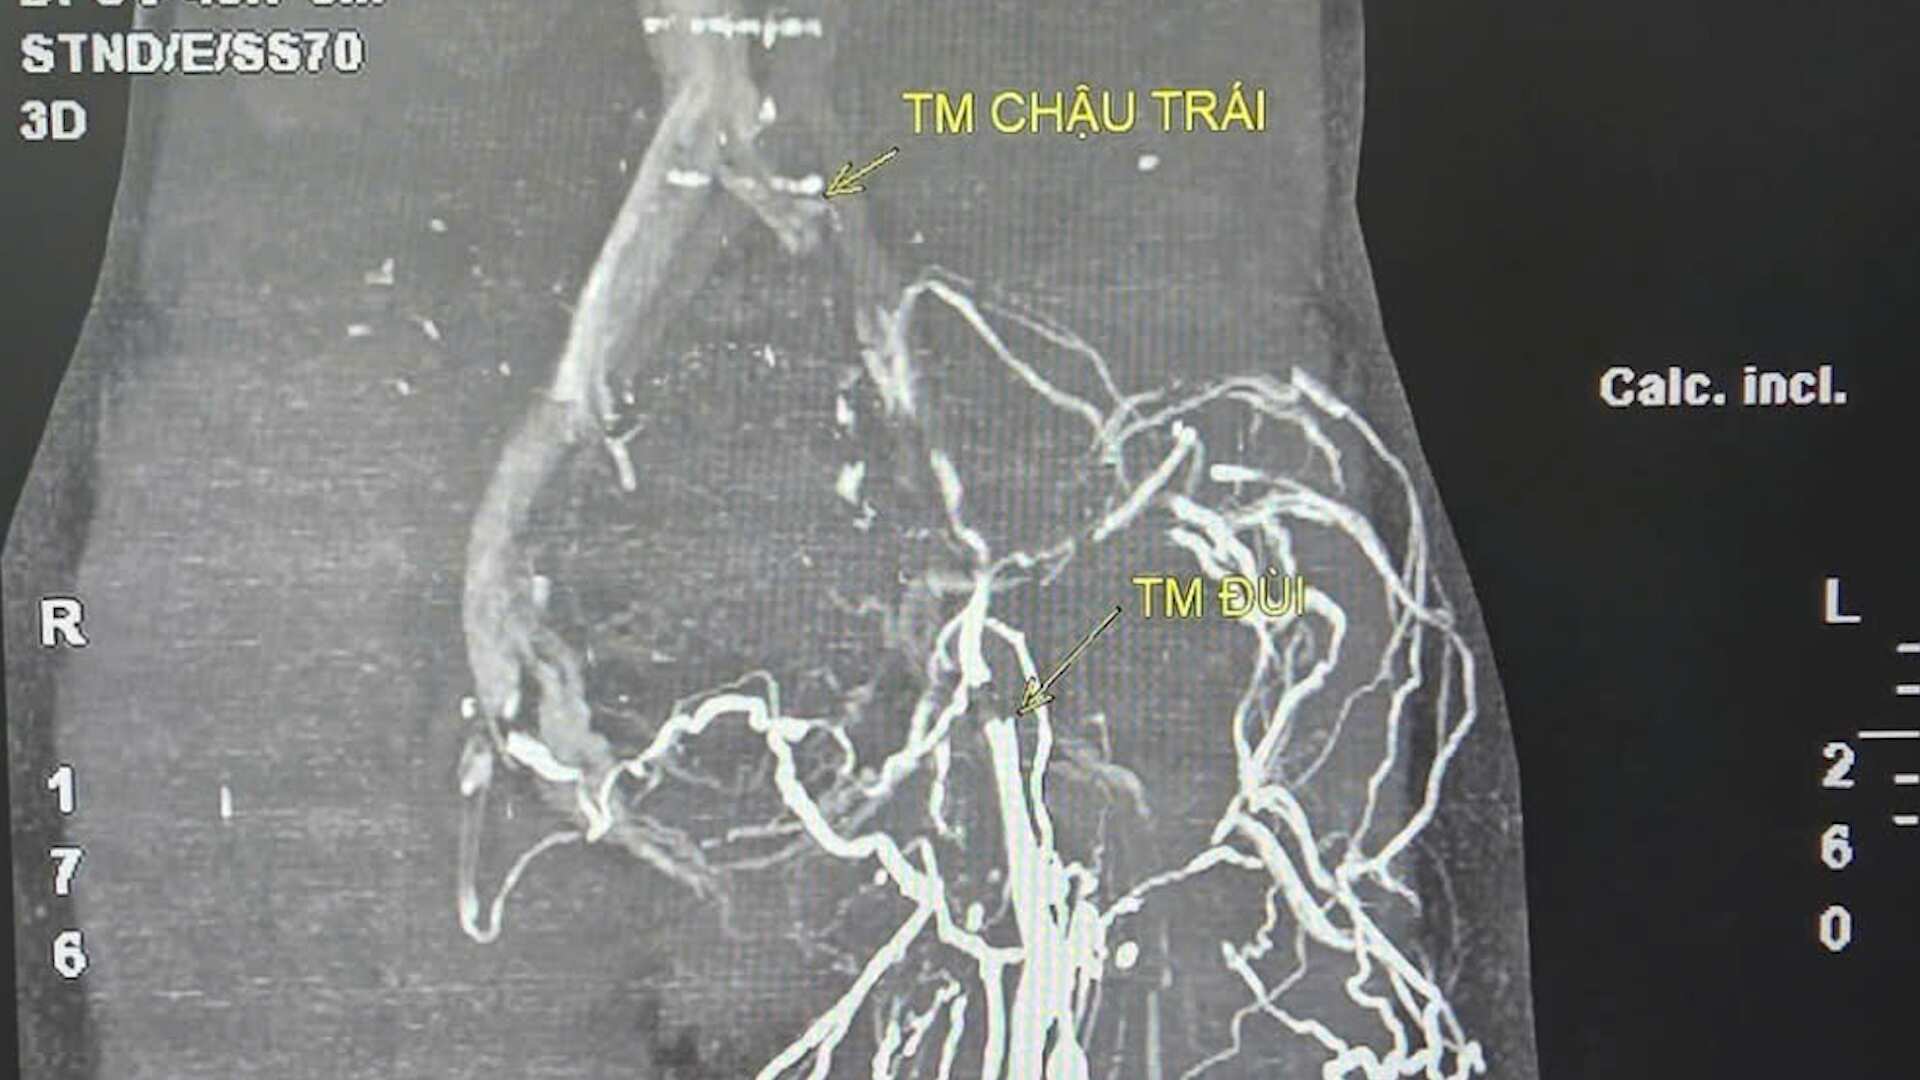

“Cuando se determino claramente la causa el equipo de intervencion se acerco al daño a traves de la arteria del muslo izquierdo identifico con precision la posicion estrecha de la arteria pelvica izquierda procedio a colocar un globo y colocar un stent debajo de la guia DSA restaurando asi la eficiencia de la circulacion sanguinea” enfatizo el Dr. Thinh.